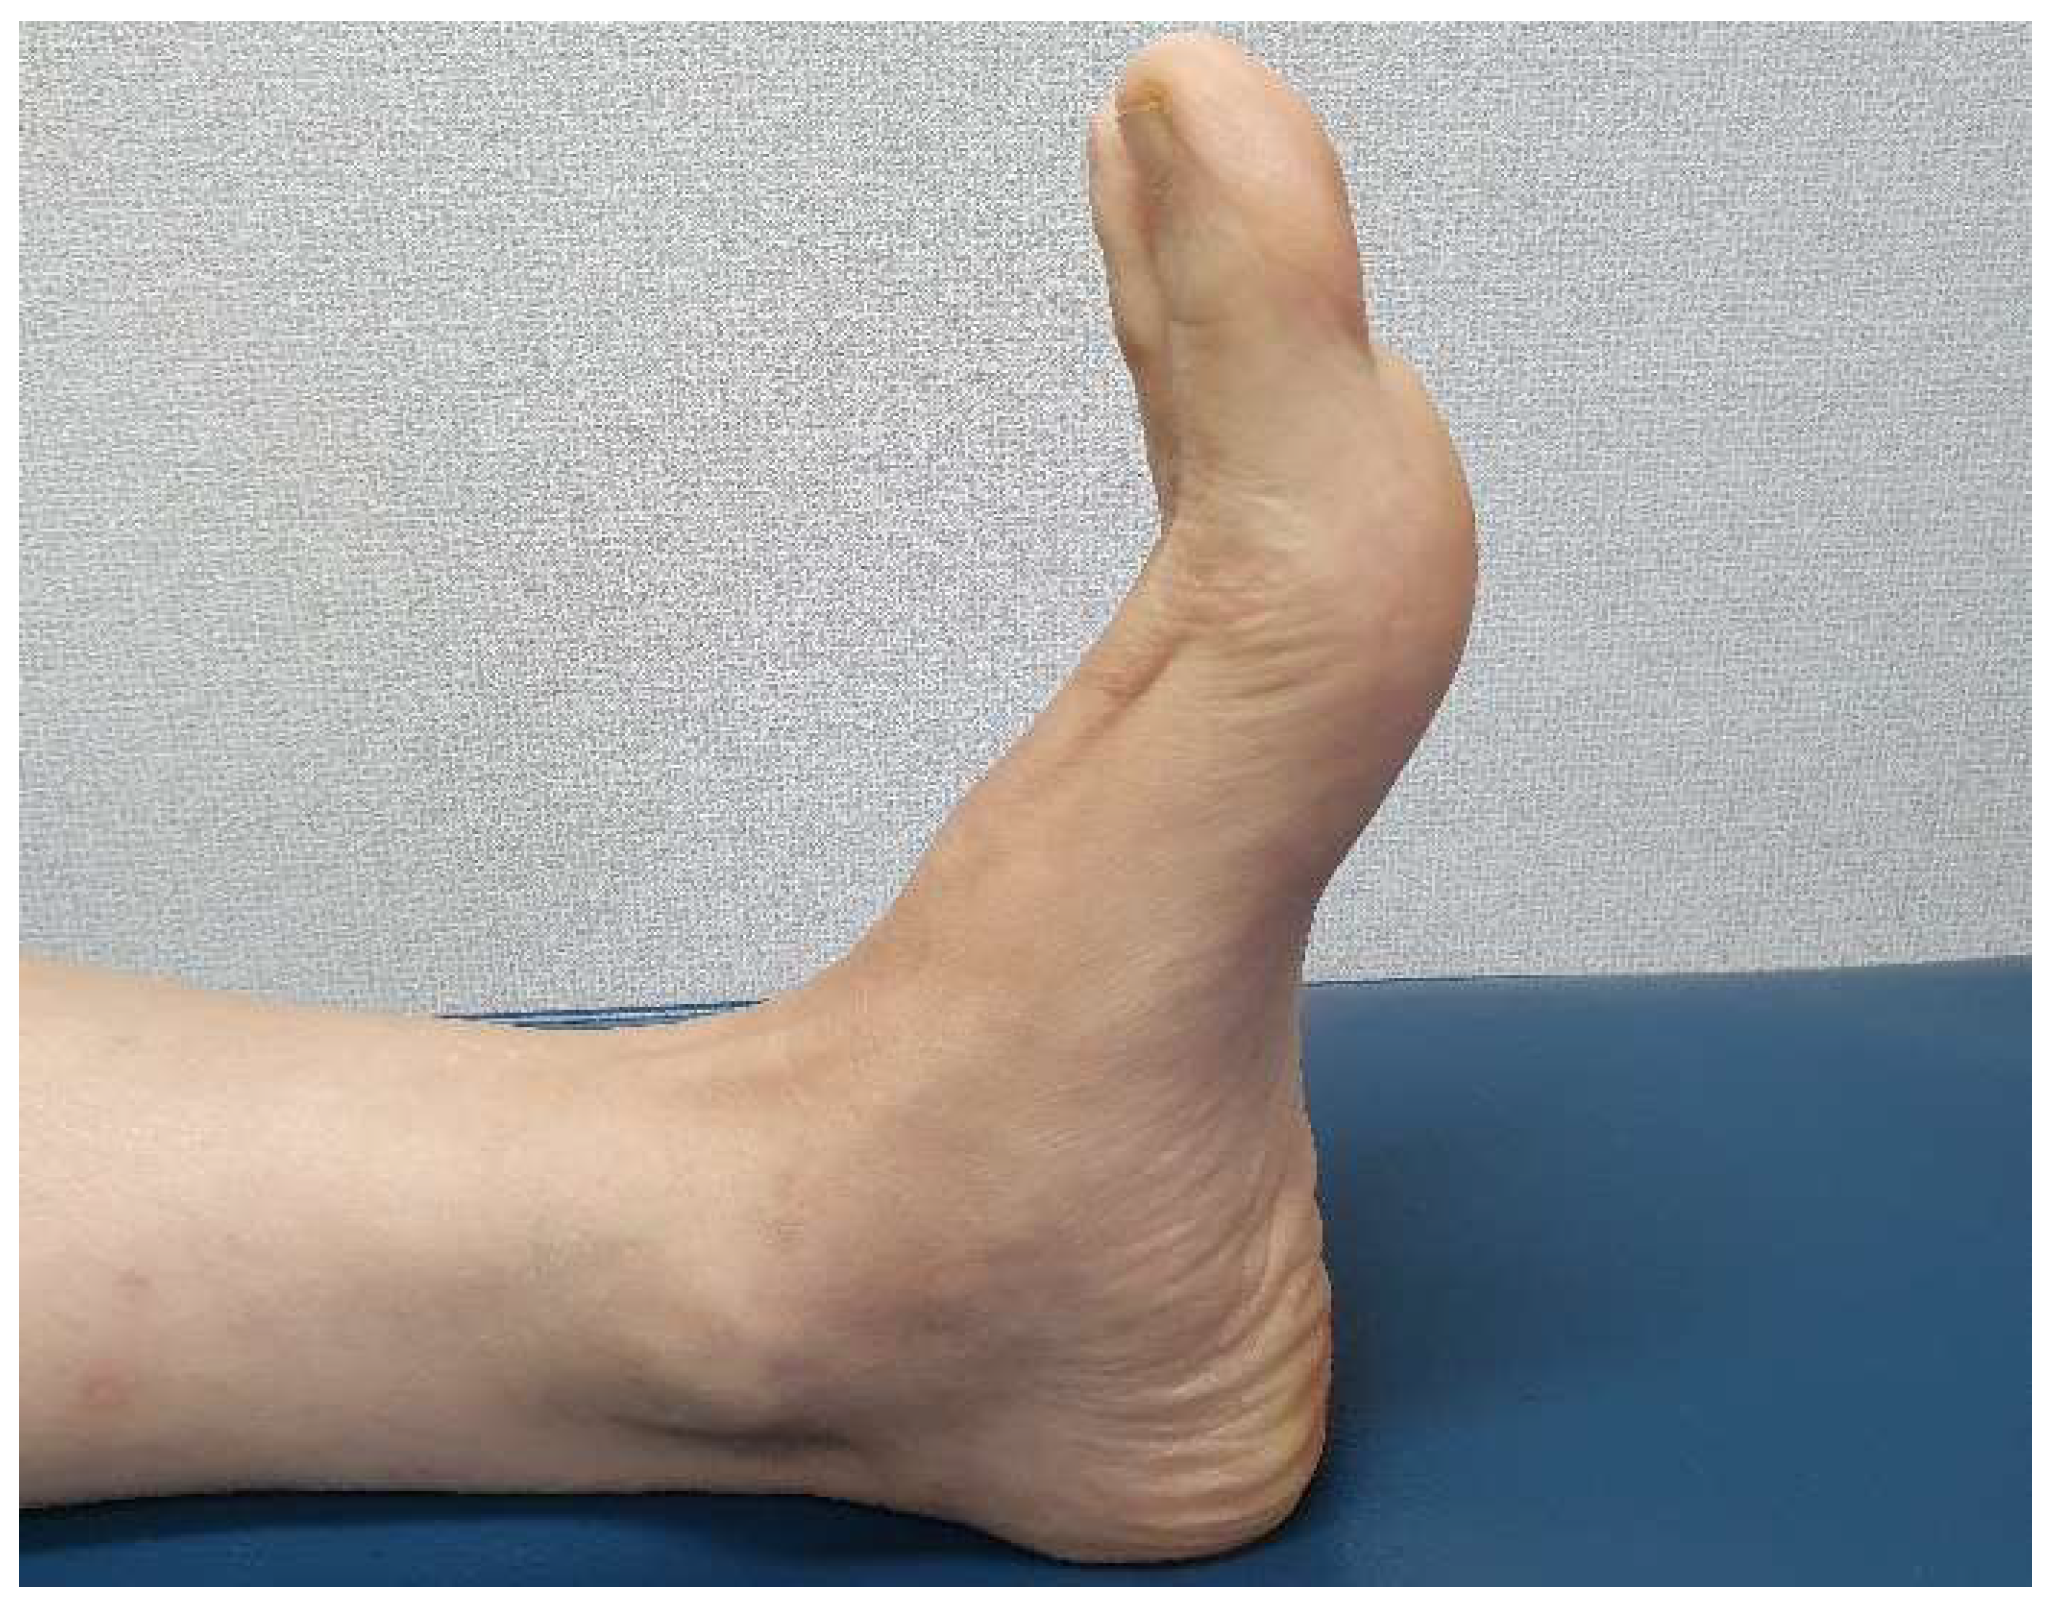

2.1. Preoperative Evaluation